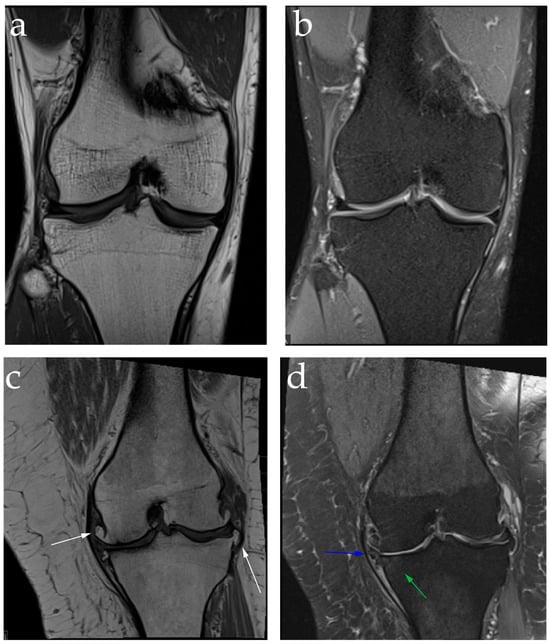

2.2. Diagnosis: Clinical Features and Image Findings